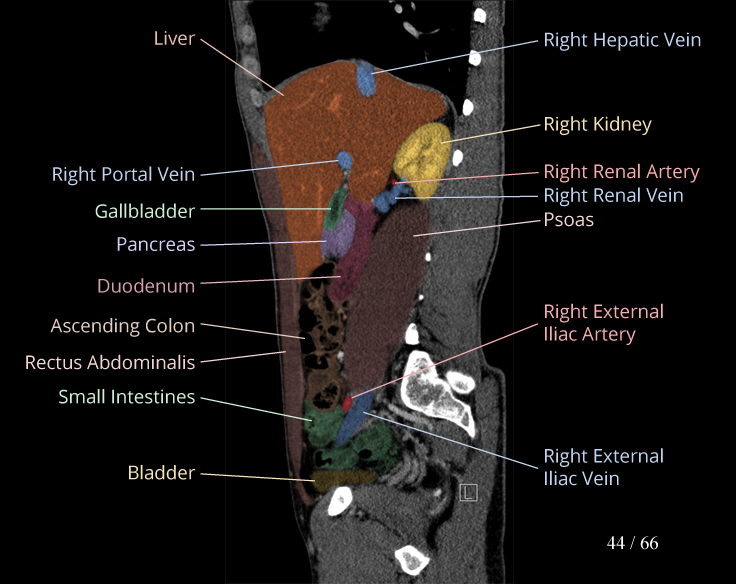

Body

Covers abdominal CT anatomy.